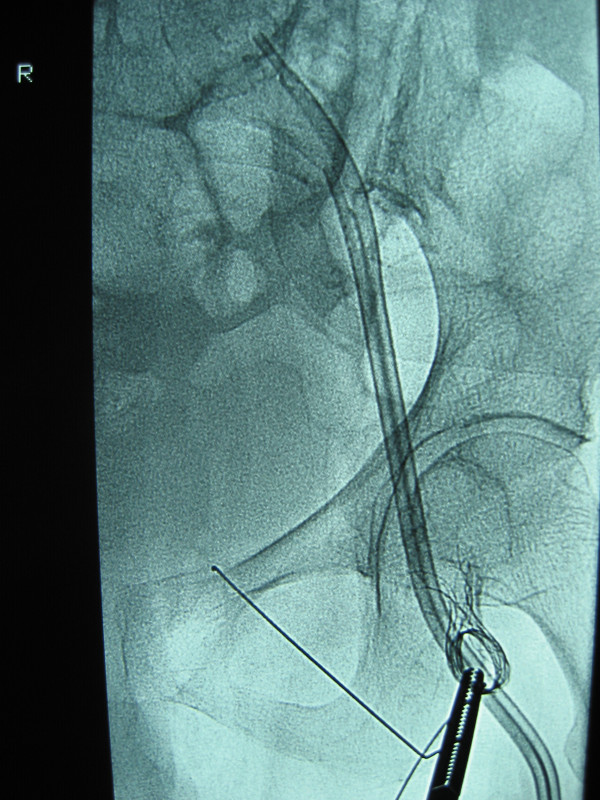

A 45 cm 10 Fr SuperArrow-flex percutaneous sheath was inserted in the left femoral vein, immediately superior to the tunnelled split-cath. Through this a 25 mm Amplatz gooseneck snare (ev3 Inc, MI, USA) was inserted and several futile attempts were made to snare the stent. A sidewinder catheter (Cordis Europa N.V) over an angled Terumo wire (Terumo Corp, Japan) was used to access the lumen of the stent. The Terumo wire, having passed through the length of the stent, was then snared through the gooseneck [Fig 3]. The snare was pulled into the sheath and a loop consisting of the sidewinder and Terumo wire was tightened, shortening the stent along its length. The constrained stent was pulled down into the left groin, the sheath and the sidewinder catheter were removed and the loop of the wire was held externally with a surgical artery clamp [Fig 4].

Figure 3.

Stent caught in Terumo wire & Snare.